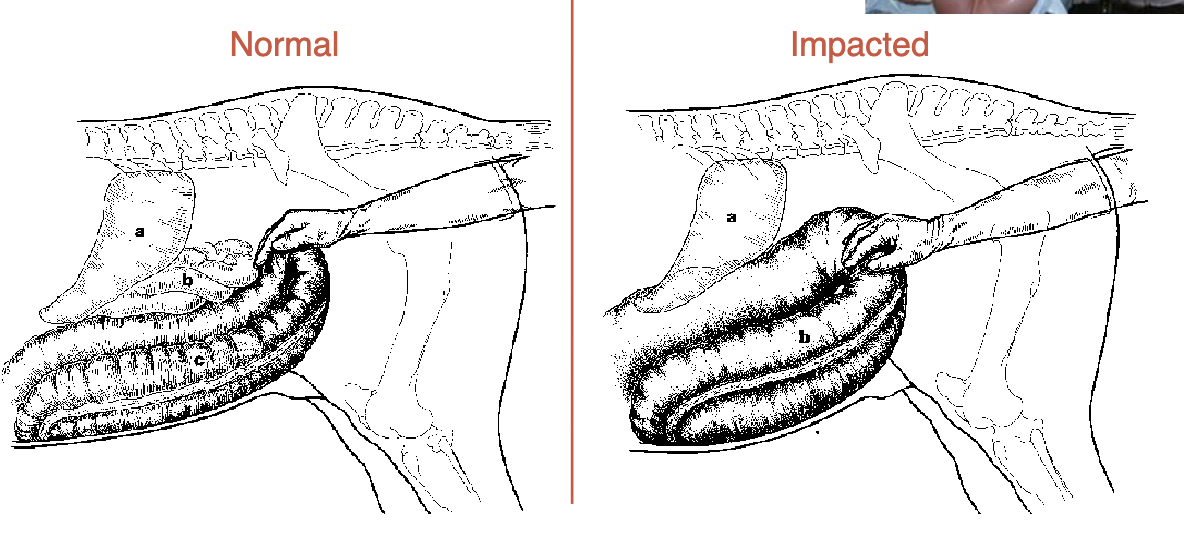

what is a common cause of colic

pelvic flexure impaction

sx→pelvic flexure enterotomy

normally, can feel at lower L of colon but when impacted it is very easily reached (at anus)

what is this

cecal impaction

sx→ typhlotomy